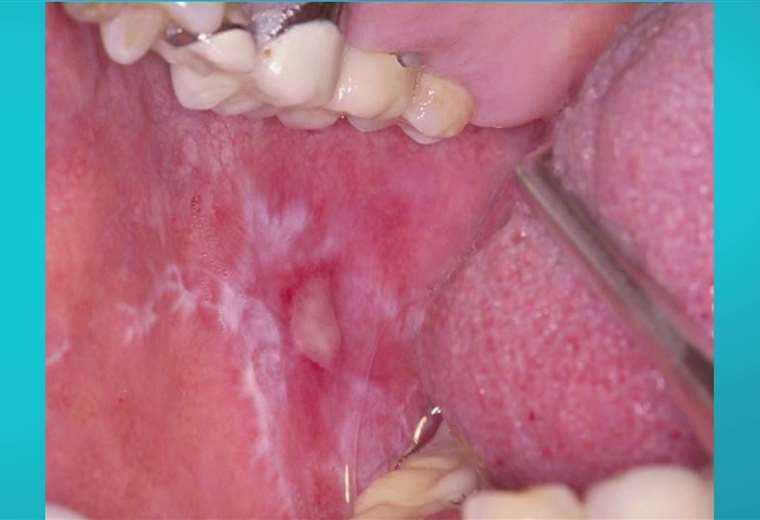

Lo más alarmante es que no da síntomas, pero su dentista podría ser el primero en identificarlo, pues las lesiones pre malignas y malignas pueden observarse en los chequeos generales o en una prueba de tamizaje bucal, que consiste es un examen odontológico simple y no invasivo.